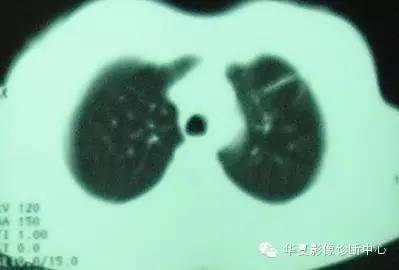

CT图像特点:双侧胸膜下片状、蜂窝状改变,肺内长条索状影向胸膜延伸。

结果:慢性嗜酸细胞性肺炎

胸部X片显示不呈段或叶性分布的周围片状阴影,常为双侧分布。糖皮质激素治疗后48h内症状和胸片可迅速消失。在同一局部可反复发生,数年后变为纤维化或蜂窝状改变。 糖皮质激素治疗效果显著,常可恢复正常,因停药较易复发,故全疗程需在一年以上。